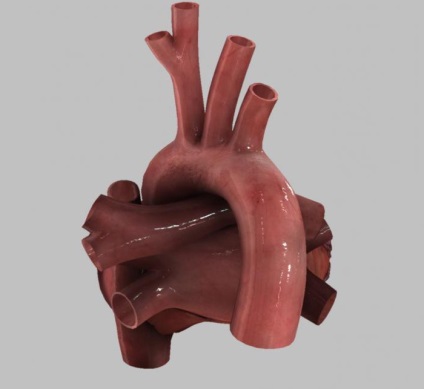

Aorta - a legnagyobb hajó az emberi szerv, amely a vért a bal kamra és az elején a szisztémás keringésbe.

Az aorta azonosított osztályok száma:

- felfelé (pars ascendens aortákat) elválasztjuk;

- Arm és ágak aortaív;

- lefelé irányuló (pars descendens aortákat) osztály, ami viszont, oszlik mellkasi és hasi részek.